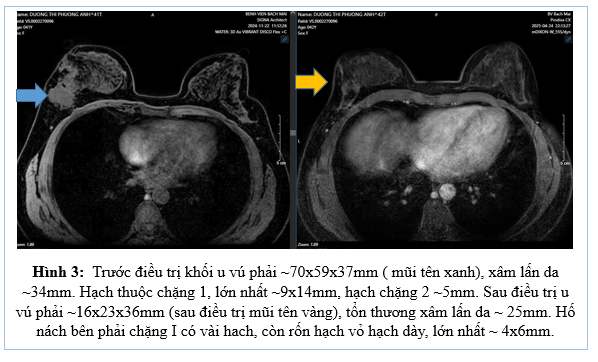

– MRI vú trước điều trị:

– CT ngực trước điều trị

Đánh giá sau 6 chu kì điều trị phác đồ TCHP

– CT ngực trước và sau điều trị tân bổ trợ

Như vậy sau 6 chu kì điều trị tân bổ trợ phác đồ TCHP cho thấy bệnh đáp ứng một phần, u và hạch giảm đáng kể kích thước. Bệnh nhân được chỉ định cắt toàn bộ tuyến vú phải và vét hạch nách (5/2025)